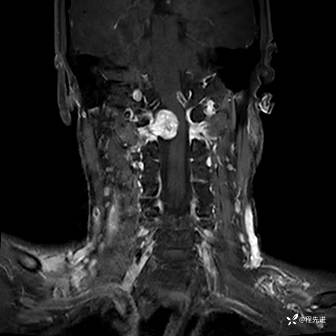

MRI平扫+增强:

T2压脂: